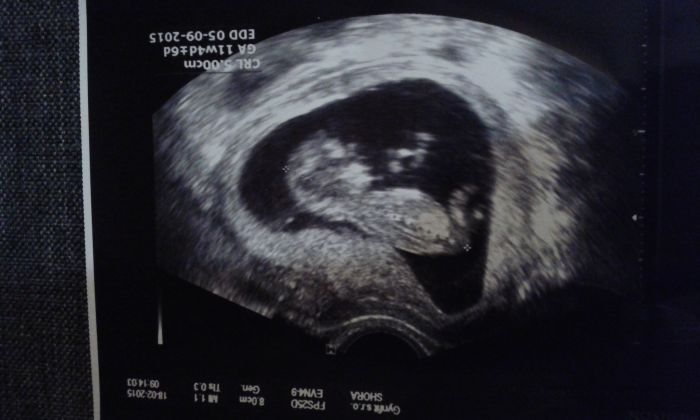

Ahoj holky, kontrola proběhla v pořádku, ale screening mi udělá až za týden, aby bylo lépe vidět projasnění a že miminko bude o trochu větší. Viděla jsem ručičky, nožičky, srdíčko jsme 11+0tt a měříme 4,1 cm . Porod máme vypočitaný na 15.9., doktor si dělal srandu, že aby nechtěl jít ven na mé narozeniny, je to nádherný pocit a jsem spokojená těhulka.